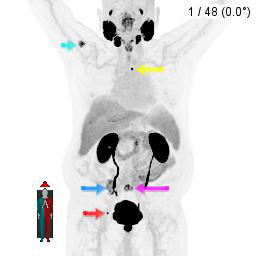

Therefore, a PSMA PET/CT was ordered, which showed (figure 1) several skeletal metastatic lesions, including the one at the site of patient’s lower back pain (figure 1, purple arrow). This patient with castrate resistant metastatic prostate cancer therefore underwent four cycles of 177Lu-PSMA-617 treatments December 2024 through April 2024. The patient reported complete resolution of lower back pain.